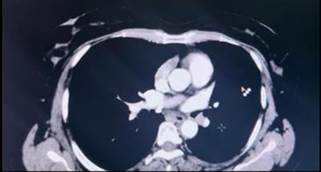

the thorax which showed a 14x12x11mm lesion in the distal main bronchus (Figure

1).

Figure 1. CECT thorax showing a well-defined enhancing lesion near the

left perihilar region.